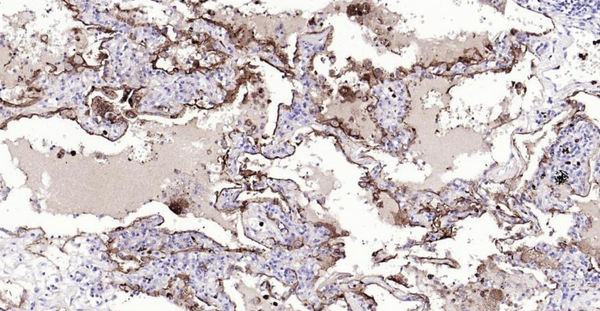

Immunohistochemical analysis of paraffin embedded human lung cancer tissue slide using IHC0132H (Human CEACAM5 IHC Kit).